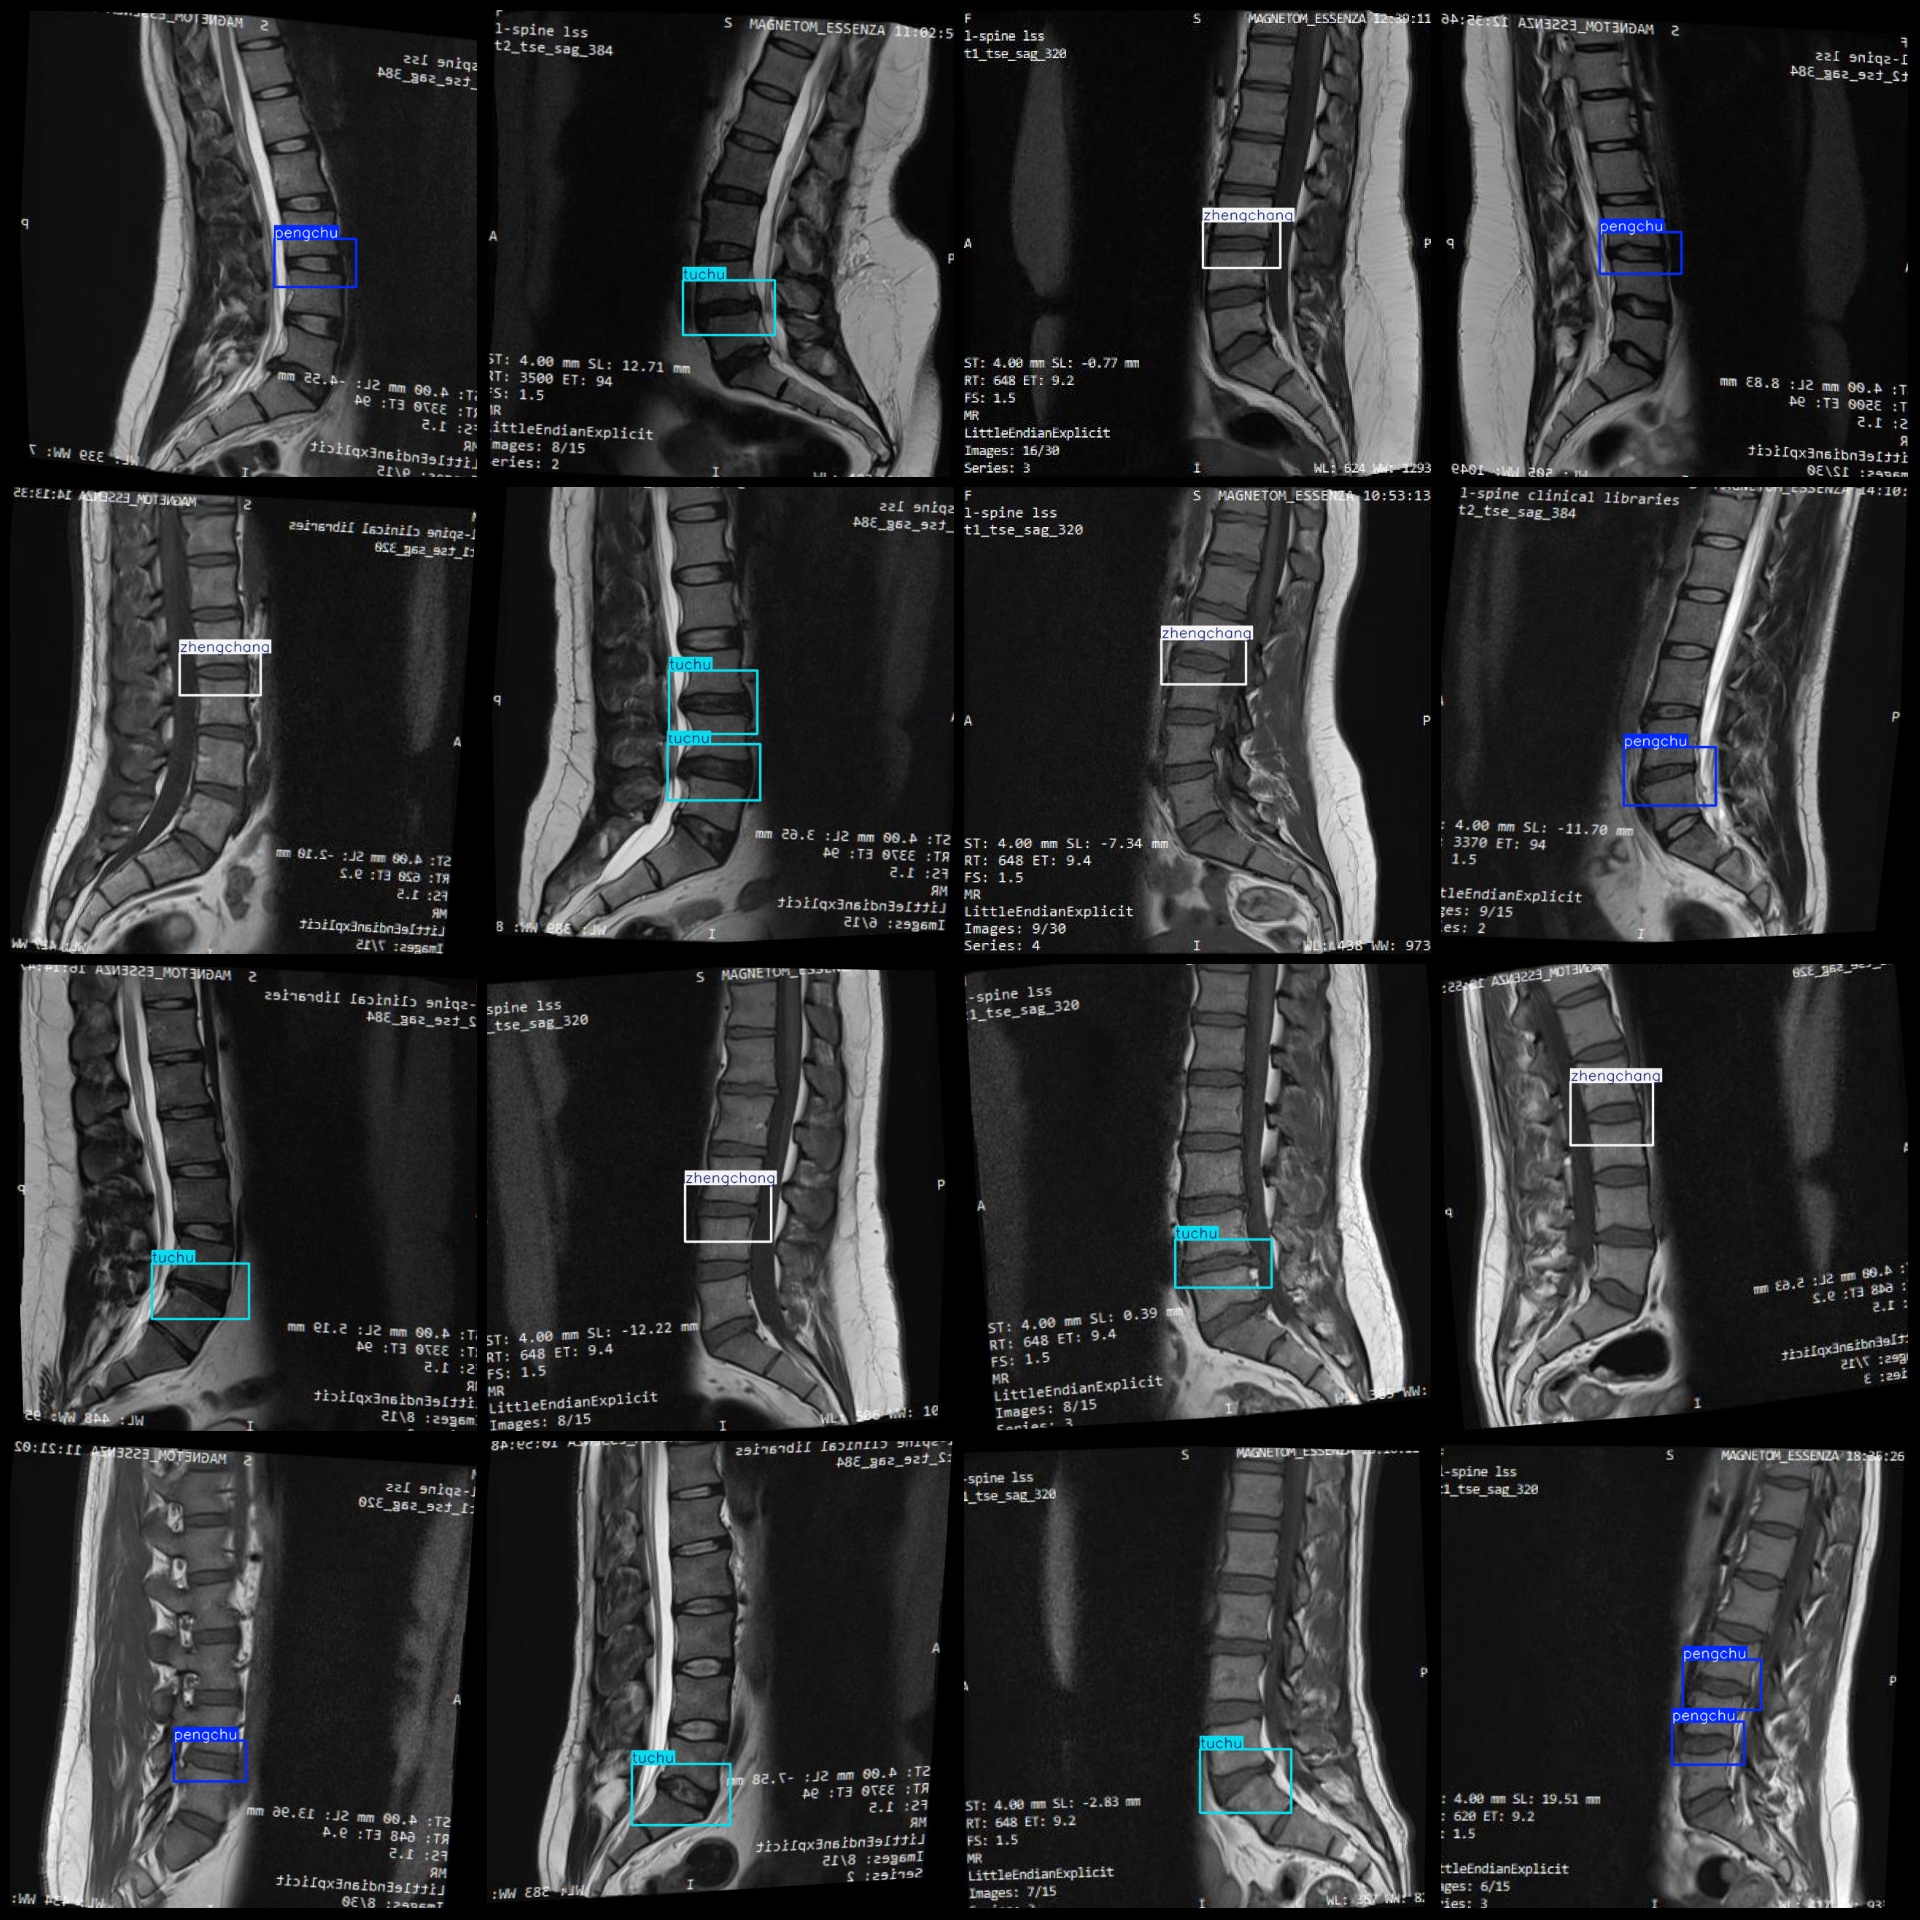

标注例子:

标注类别名称(注意yolo格式类别顺序不和这个对应,而以labels文件夹classes.txt为准):["pengchu","tuchu","zhengchang"]

pengchu(膨出) 框数 = 274

tuchu(突出) 框数 = 266

zhengchang(正常) 框数 = 282